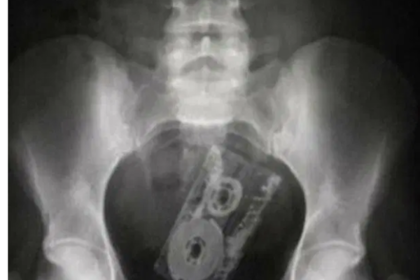

Доктора поделились рентгеновскими снимками, на которых в анальных отверстиях людей запечатлены различные предметы. Об этом сообщает The Sun.

Все эти вещи врачам пришлось удалять хирургическим путем. Один из докторов сообщил в Twitter, что секс-игрушки должны продаваться со специальными шнурами для удаления. Хирург возмутился, что ему пришлось провести слишком много подобных операций.

Врачи рассказывали, как удаляли воронку, огурец, упаковку с таблетками или лампочку. Кто-то находил в анальных отверстиях пациентов бокалы для шампанского и даже зонтик.

Поделилась своей историей и врач, которая удалила целую ветвь с яблоками из прямой кишки пациента. Ее американский коллега рассказал, что однажды извлек «самую полезную находку» — это был футляр для очков с аксессуаром внутри. Доктора добавили, что секс-игрушки безопаснее, чем различные предметы из бытового обихода.

Профессор Нил Мортенсен, вице-президент Королевского колледжа хирургов, призвал людей обращаться за медицинской помощью как можно скорее, если в прямую кишку попал инородный предмет. Мортенсен добавил, что этого не надо стесняться, так как врачи в больнице уже насмотрелись таких случаев. Он отметил, что высок риск заразиться инфекцией или получить серьезные болезни.